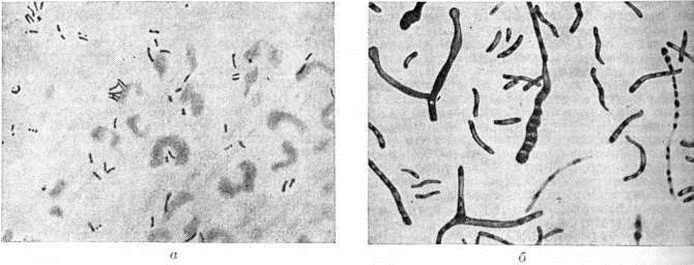

Микобактерии Туберкулёз— тонкие, прямые или слегка изогнутые палочки длиной 1 —10 (чаще 1—4) микрометров шириной 0,2—0,6 микрометров, гомогенные или зернистые со слегка закруглёнными концами (рисунок 1, а). Они неподвижны, не образуют эндоспор, конидий и капсул. Морфология и размеры бактериальных клеток подвержены значительным колебаниям, что зависит от их возраста и особенно от условий существования и состава питательной среды.

Микобактерии Туберкулёз весьма устойчивы к воздействию факторов окружающей среды, характеризуются выраженным многообразием форм существования, большим полиморфизмом и широким диапазоном изменчивости биологический свойств (плеоморфизм). Описаны многочисленные морфологический варианты микобактерий: гигантские формы с колбовидно-утолщёнными разветвлениями, нитевидные, мицелиеподобные и булавовидные, дифтероидные и актиномикотические формы (рисунок 1, б). Микобактерии Туберкулёз могут быть длиннее или короче обычных, толще или тоньше, гомогенными или зернистыми. Иногда они представляют собой цепочки или отдельные скопления кокковидных зёрен. Микобактерии Туберкулёз способны образовывать фильтрующиеся формы, биологическая и патогенетическая роль которых окончательно не выяснена. Описаны биологический свойства и изучена патогенетическая роль L-форм микобактерий Туберкулёз (смотри полный свод знаний: L-формы бактерий), обусловливающих различные клинические, проявления процесса.